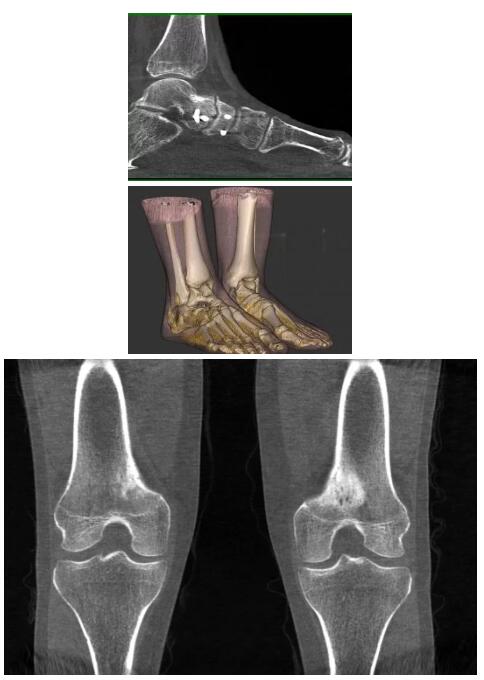

比如上面這款專用于足部和踝部掃查的CT成像系統(tǒng),患者在進(jìn)行CT掃查時只需要站在上面即可,雙腳站或者單腳站都可以,當(dāng)然,如果患者不是那么方便站著做完CT掃查,也可坐在上面。

這款CT掃查系統(tǒng)自帶屏蔽裝置,它的體積非常小,僅需要極小的空間即可,并不像常規(guī)CT那樣需要一間單獨的檢查室。此外,這種CT掃查的速度非???,僅需30秒左右可以完成檢查,輻射劑量相對常規(guī)的CT要少許多,尤其適合醫(yī)院的骨科使用。

而患者站著做足部或者踝部做CT檢查還有個好處是,可以檢查患者在負(fù)重的情況下,骨關(guān)節(jié)的真實情況,而躺著做CT掃查時未必能看出來。負(fù)重CT掃查特別是對于受傷的運(yùn)動員或者舞蹈員來說意義更大,能夠更準(zhǔn)確地評估傷情,幫助他們盡早復(fù)原。

以下是這些“特立獨行”的CT所拍出來的圖像: